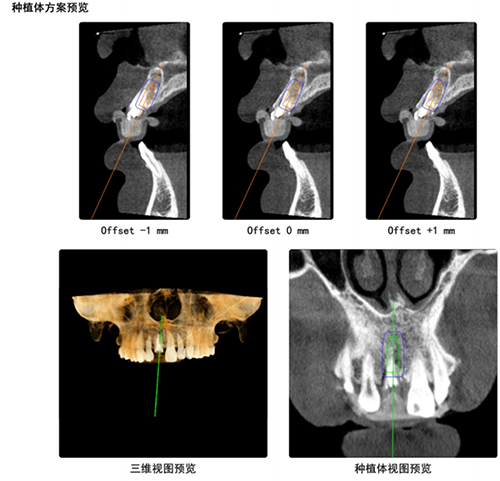

术前,张东升、黄圣运详细评估了患者情况,结合既往应用手术导航设备的经验,应用数字化种植导航设计软件,对患牙CBCT进行了全面分析,根据缺牙区实际骨量,选择了最适种植体系统及型号,并设计了最优化种植体植入位点和方向,为本次手术的顺利进行奠定了坚实的基础。